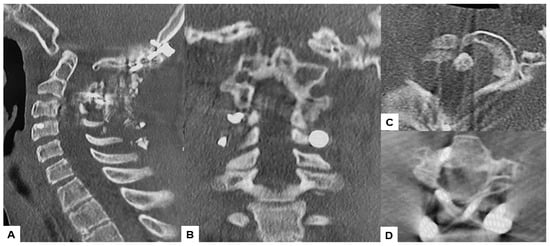

2.6. One Year Follow-Up